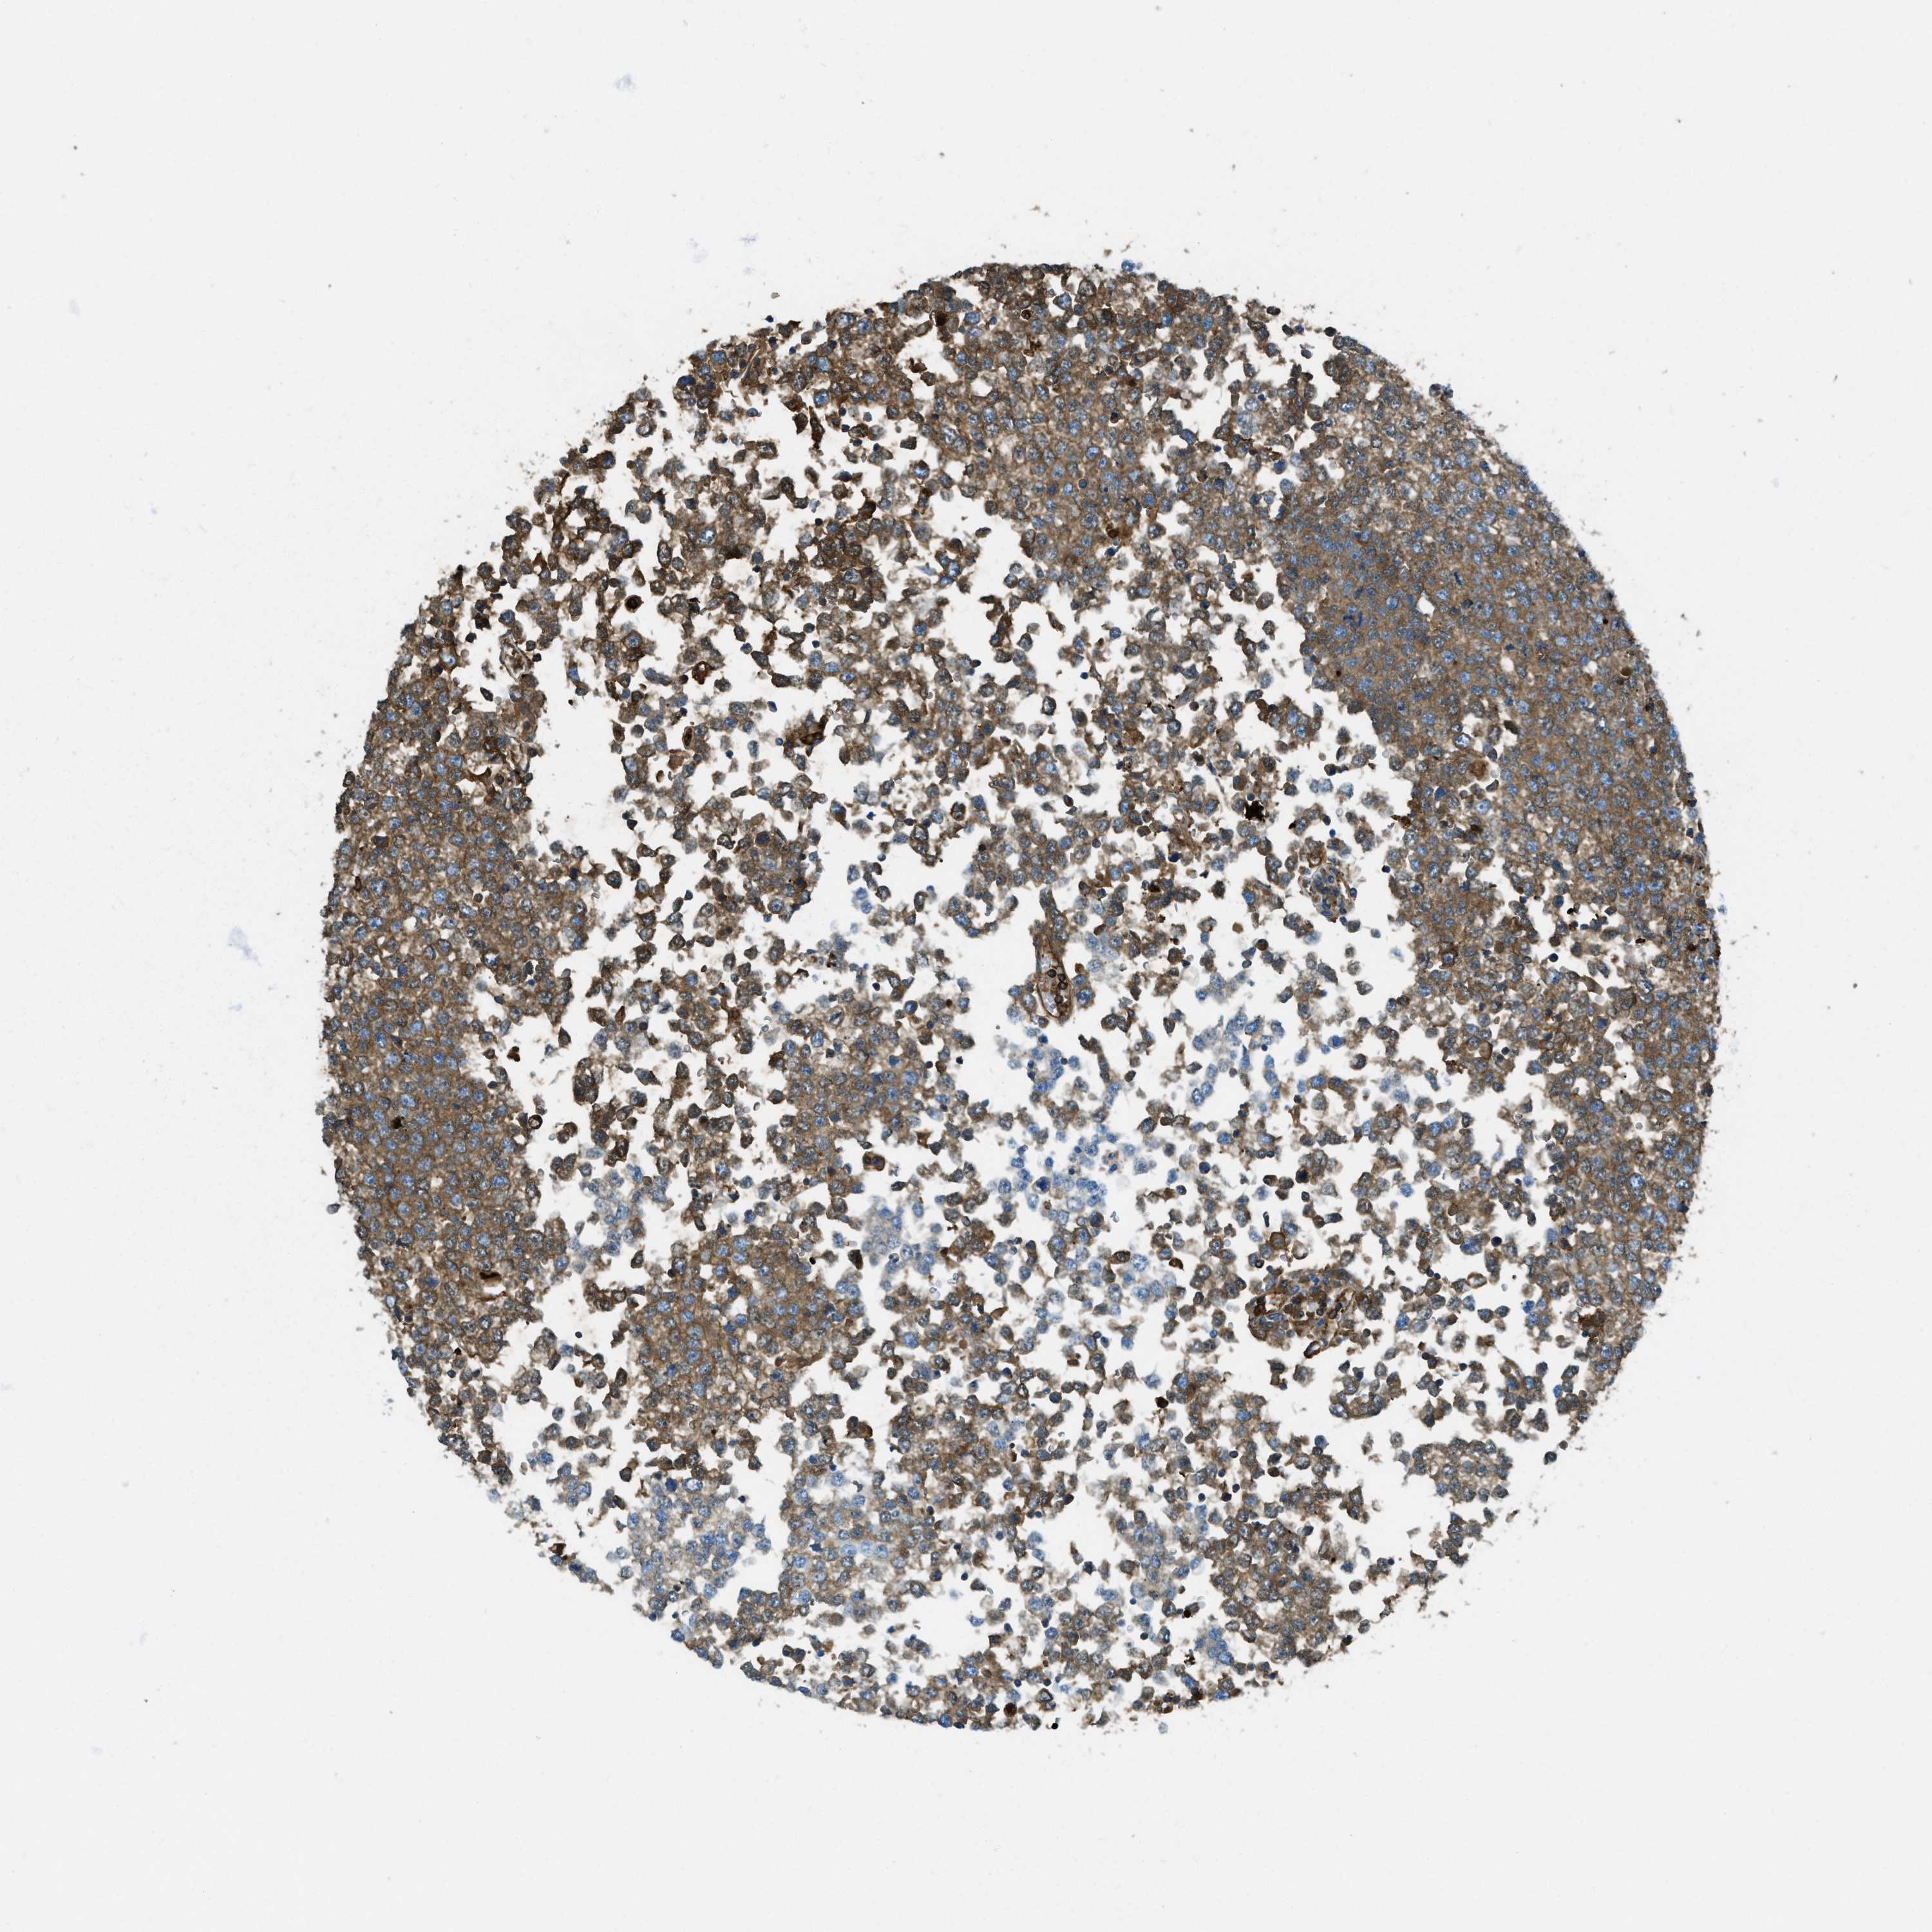

TESTIS CANCER - Protein expressioni

A mouse-over function shows sample information and annotation data. Click on an image to view it in a full screen mode. Samples can be filtered based on level of antibody staining by selecting one or several of the following categories: high, medium, low and not detected. The assay and annotation is described here.

Note that samples used for immunohistochemistry by the Human Protein Atlas do not correspond to samples in the TCGA dataset.

Antibody stainingi

Antibody staining in the annotated cell types in the current human tissue is reported as not detected, low, medium, or high, based on conventional immunohistochemistry profiling in selected tissues. This score is based on the combination of the staining intensity and fraction of stained cells.

Each image is clickable and will lead to virtual microscopy that enables deeper exploration of all samples and also displays staining intensity scores, fraction scores and subcellular localization as well as patient and tissue information for each sample.

Antibody HPA017750

Staining

High

Medium

Low

Not detected

Intensity

Strong

Moderate

Weak

Negative

Quantity

>75%

75%-25%

<25%

None

Location

Nuclear

Cytoplasmic/membranous

Cytoplasmic/membranous,nuclear

Carcinoma, Embryonal, NOS

Seminoma, NOS